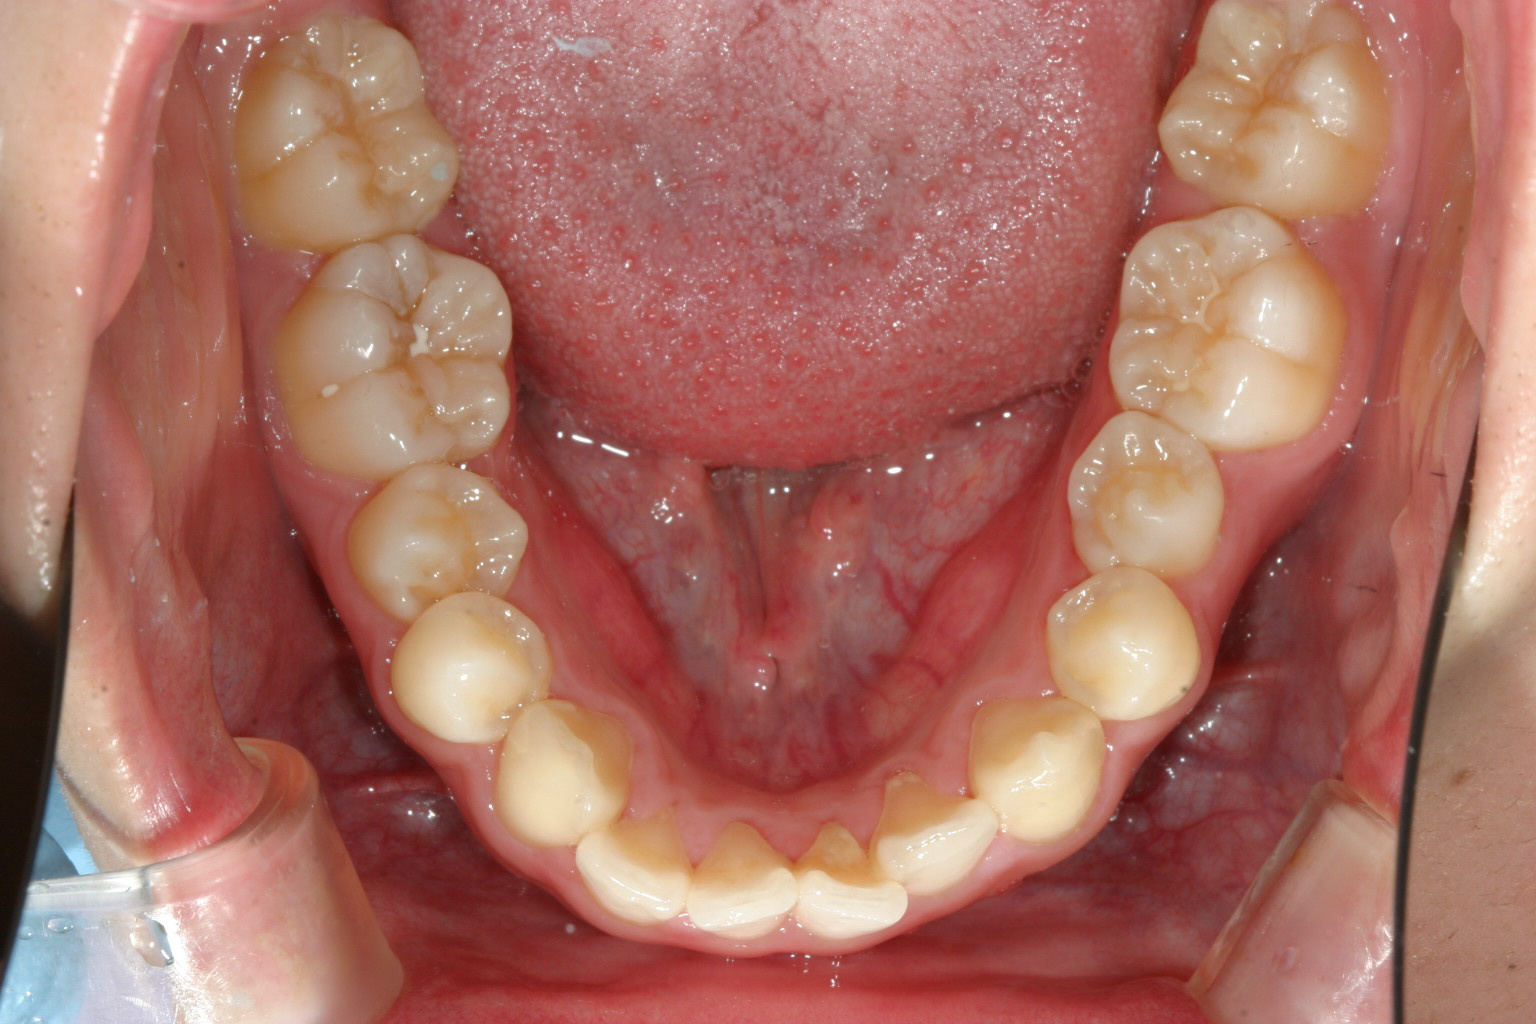

下顎もアーチが尖っていますね!

下顎も綺麗なアーチになりました。